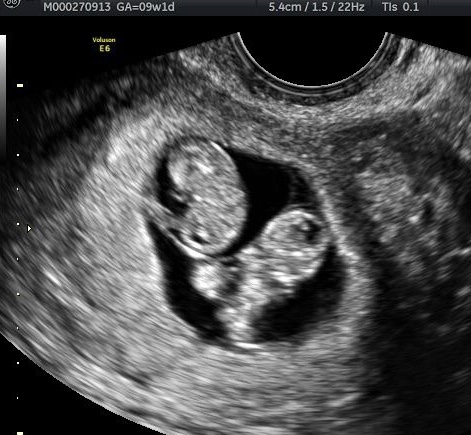

Identical Twins After Reversing Burned Tubes!

Review #3111

Reversing Burned Tubes With Dr Monteith

identical-twins-after-reversing-burned-tubal-ligationDr. Monteith

Having confirmed same sac twins…our identical twins!

Patient age: 42

Tubal ligation type: Coagulation (burned)

Patient hometown: Orting, Washington